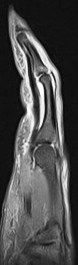

37 y/o male 4th finger injury with pain.

Annular pulley tears result in bowstringing of the tendon. Compare the sagittals of the 4th finger with the sagittal of the 5th finger which is not bowstrung (5th is labeled). I dont believe I have recognized only half of the pulley torn before.

Ulnar aspect A3 pulley tear with bowstringing of the flexor tendons